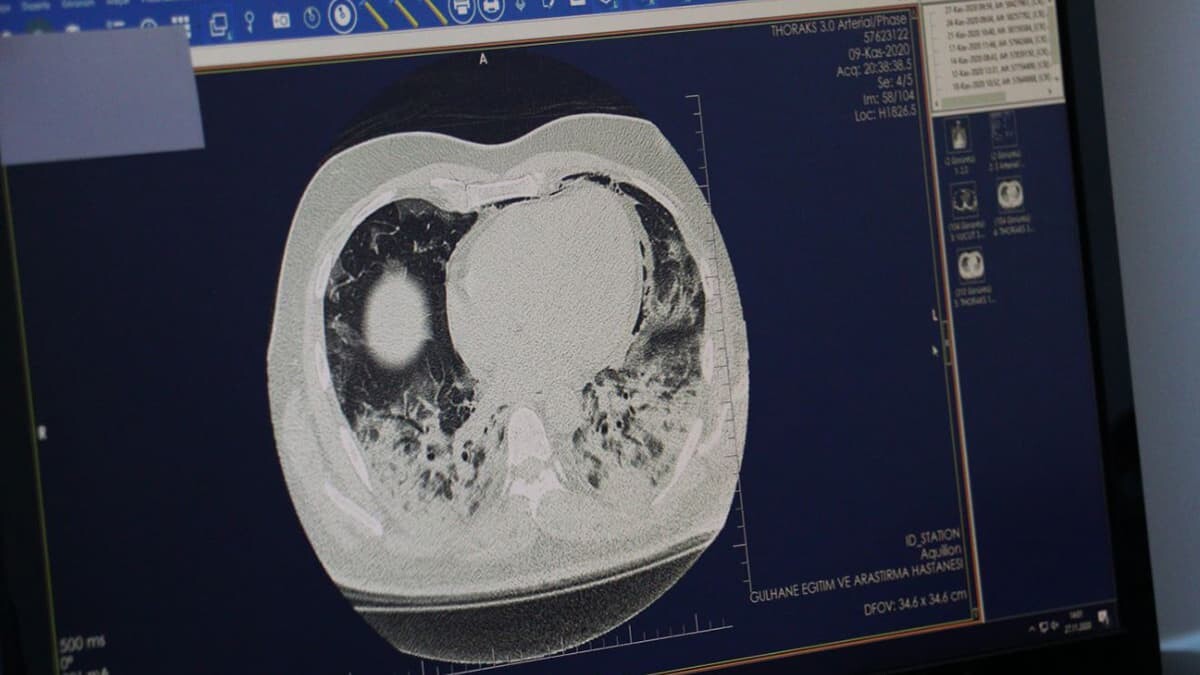

Ankara Sağlık Bilimleri Üniversitesi Gülhane Eğitim ve Araştırma Hastanesi Göğüs Hastalıkları Uzmanı Doç. Dr. Cantürk Taşçı, hastalara ait tomografi görüntüleri üzerinden Covid-19‘un akciğerde yarattığı tahribatı anlattı. Doç. Dr. Taşçı, “Covid-19, akciğerdeki solunum keseciklerinde hasara yol açıyor. Orada bir sertleşme, büzüşme, solunum keseciklerinin fonksiyonlarını yitirmesine neden oluyor. Bu, yaygınlığı, şiddeti arttıkça hastaları solunum yetmezliğine götürebiliyor” dedi.

Sağlık Bilimleri Üniversitesi Gülhane Eğitim ve Araştırma Hastanesi’nde Covid-19 tedavisi gören hastaların akciğerlerindeki tahribat, tomografi görüntülerine yansıdı. Görüntülerde, hastalığın ne kadar hızlı ilerlediği, akciğeri nasıl tuttuğu ve yarattığı hasar gözler önüne serildi. Göğüs Hastalıkları Uzmanı Doç. Dr. Cantürk Taşçı, Covid-19’un akciğere girişini ve bıraktığı hasarı anlattı. Prof. Dr. Taşçı, “Koronavirüs ağız ve burundan akciğerlerimize ulaşabilmekte, tek giriş yolu burası. Tabii her hastamızda akciğere ulaşım olmuyor. İmmün sistemi sağlam olan kişilerde, daha çok gençlerde bu virüs üst solunum yollarında kalabiliyor. Bunlarda daha çok kısmi semptomlarla, hatta aseptomatik olarak seyredebiliyor. Akciğerde tutulma olmadan gribal semptomlar ile bu hastalığı atlatabiliyorlar” dedi.

Doç. Dr. Taşçı, koronavirüsün akciğerdeki solunum keseciklerinde hasara yol açtığını kaydederek, “Orada bir sertleşme, büzüşme, solunum keseciklerinin fonksiyonlarını yitirmesine neden oluyor. Bu, yaygınlığı, şiddeti arttıkça hastaları solunum yetmezliğine götürebiliyor. Ama dediğim gibi her hastada farklı seyretmekte. Hastanın kendi bağışıklık sisteminin gücüyle beraber bazı hastalarda solunum yetmezliğine, bir kısım hastada yoğun bakıma kadar ilerleyebilmekte.

Bazı hastalarda çok yaygın akciğer büzüşmesi denilen tabloya yol açıyor. Tabii ki bu hastaları biz yine iyileştiklerinde taburcu ediyoruz; ama akciğerdeki düzelmeler akciğer büzüşmesi oluştuysa ayları bulabiliyor. Onun dışında o kadar şiddetli değilse taburcu olduktan yaklaşık 1 hafta 10 gün sonra akciğerleri tamamen normale de dönebiliyor. Akciğerde kalıcı hasar şu ana kadar gördüklerimizde yok. Hastaları kontrollere çağırıyoruz, akciğer hasarı takiplerimizde hemen hemen yok” ifadelerini kullandı.